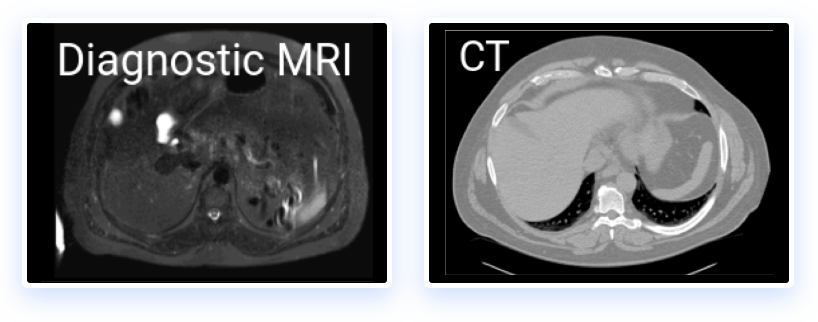

Reformat registered images to see sagittal, coronal and axial views from multiple 3D modalities: